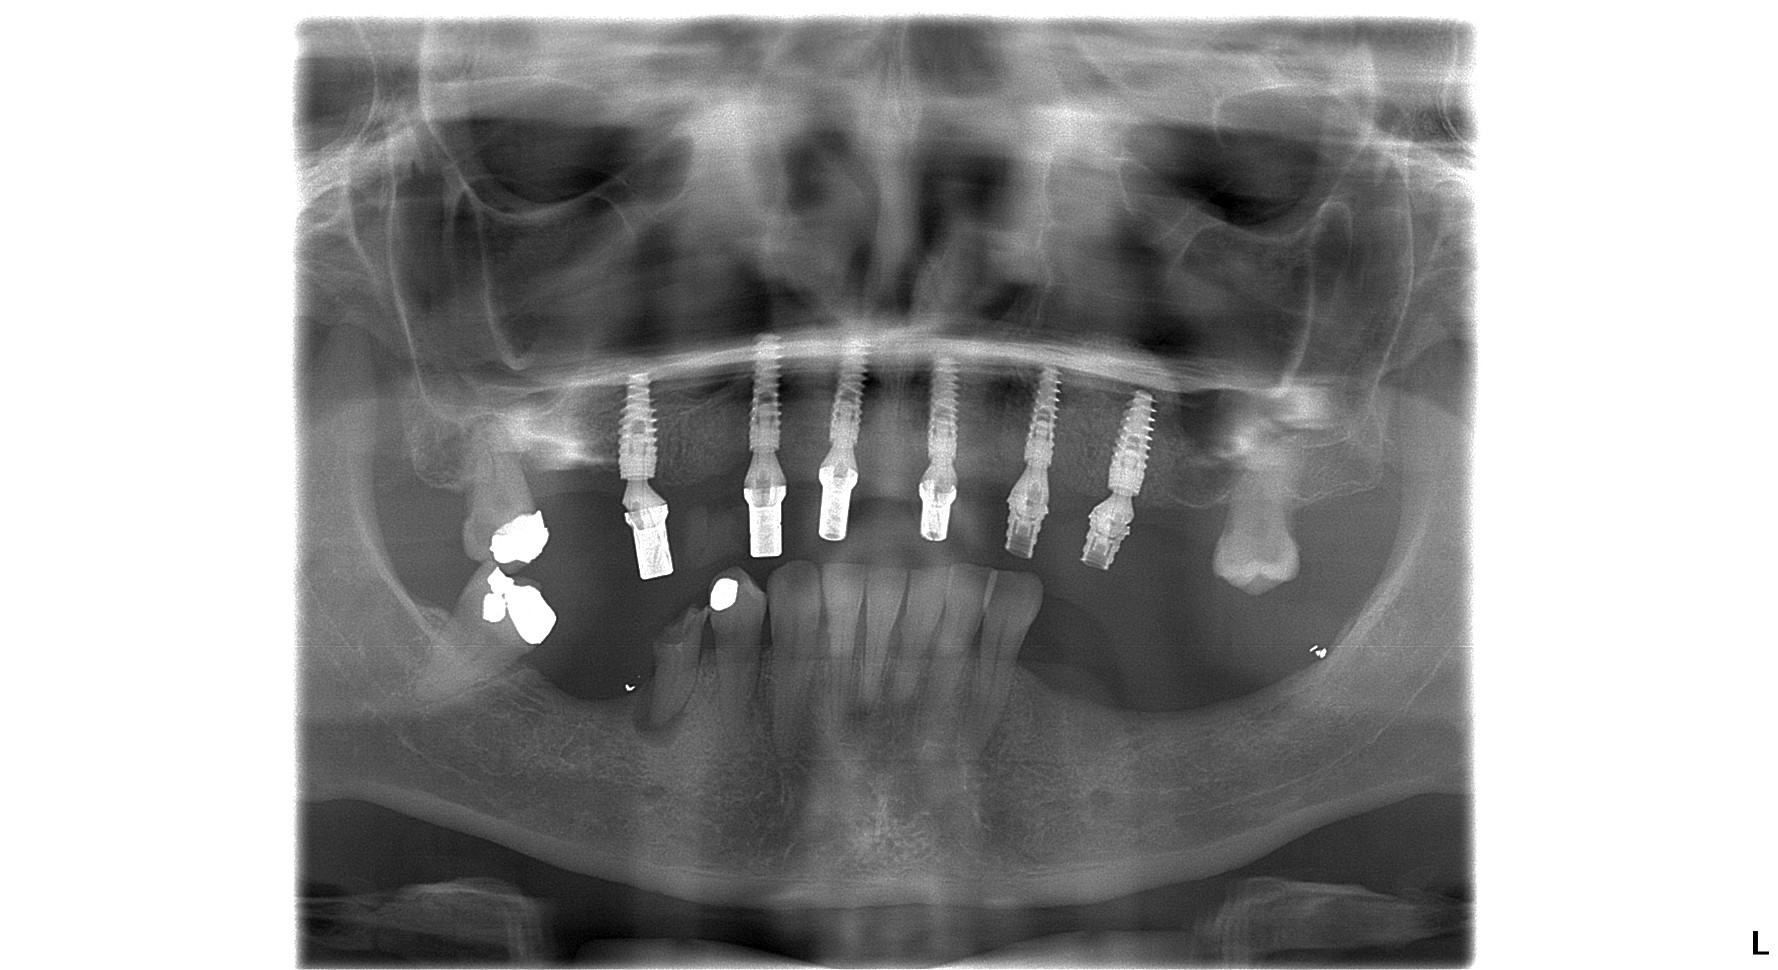

The Smile Clinic in Slovakia is one of the most well-equipped dental clinics in the country, hence our 4* platinum rating by the GCR. Therefore prior to the consultation with our dental implant specialist Dr. Marek, one of our dental nurses, who speaks fluent English took a dental OPG X-ray and 3D CBCT scan for Margaret. After the dental consultation, an oral health examination and a detailed review of the dental X-ray and CT scan, Dr. Marek prepared a personalized treatment plan for Margaret.

On the very same visit Dr.Marek and his team placed 6 dental implants for Margaret. Our team members at dental lab prepared a temporary bridge for Margaret to wear while she was having surgery. After the implantation a fixed temporary bridge is usually fitted for patients. This special bridge has titanium reinforcement for better stability and patients can travel back home comfortably with teeth that they can smile and eat comfortably with! We cannot bear the fact that we’d send someone home with false teeth for the healing period, as our patients, even in-between appointments are a walking advertisement for our clinic.